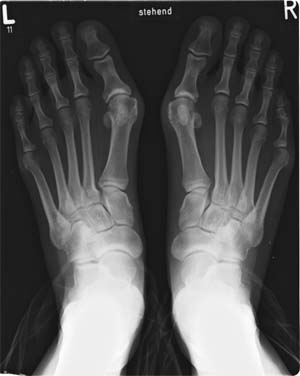

Hallux valgus is een standsafwijking van de grote teen. De grote teen staat hierbijnaar buiten gericht, zie de röntgenfoto rechts (bron: Michael Nebel).

Hallux valgus wordt vastgesteld door lichamelijk onderzoek, gecombineerd met een röntgenfoto om te kijken of er ook slijtage is van het teengewricht tussen het middenvoetsbeentje en de grote teen. Ook kan op deze röntgenfoto gezien worden hoe ernstig de standsafwijking is. Dit kan worden opgemeten en in graden worden uitgedrukt.